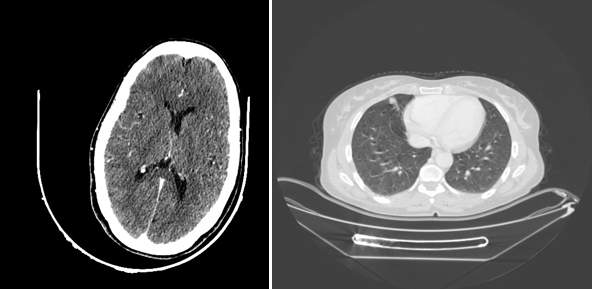

Figure 3 Scanographic image: on the left at the cerebral level: a cross section of the C+ skull not showing an image related to a secondary location, unlike the thoracic level: showing a right lower lobe nodule.

Then, a TAP CT scan looking for distant metastasis demonstrated the presence of pulmonary nodules in the upper and middle right lobes related to secondary locations (Figure 3).

Figure 1 Intraoperative image showing the presence of molar vesicles exceeding the serosa of the globular uterus, with a heterogeneous-looking ovary.

And so, the pelvic MRI was in favor of a gestational trophoblastic tumor invading the serosa coming into contact with the ovary and the rectum posteriorly measuring 65*45mm associated with thrombosis of the left internal iliac vein and the homolate ovarian vein, just as a Hemoperitoneum of low abundance (Figure 4).